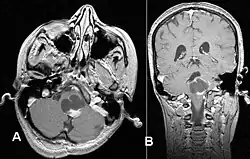

Este tumor se presenta generalmente como una lesión circunscrita y bien delimitada, de crecimiento lento y puede ser sólido o quístico.[2] Suelen apreciarse con facilidad en las imágenes de TC y RM. Los quistes pueden ser monoloculares o multiloculares, con el nódulo tumoral encapsulado en el interior. El astrocitoma pilocítico generalmente aparece a nivel del cerebelo, tronco cerebral, región hipotalámica, nervios y quiasma óptico, y en general en cualquier área donde haya presencia de astrocitos, incluyendo los hemisferios cerebrales y la médula espinal. La localización más frecuente es el cerebelo.[3]

El diagnóstico de este tumor se lleva a cabo normalmente usando la tomografía computarizada (TC) o la resonancia magnética nuclear (RM) del cráneo, con medio de contraste. De manera complementaria, puede añadirse una tomografía por emisión de positrones (PET).[8]

La RM ofrece una mayor sensibilidad en comparación con la TC, si bien no siempre es fácilmente accesible y presenta contraindicaciones, por ejemplo, no se puede utilizar en pacientes con marcapasos, prótesis incompatibles con el campo magnético, clips metálicos, etc. En las imágenes de TC y RM el astrocitoma pilocítico aparece como un tumor con márgenes bien definidos, redondeado, sólido o asociado a macro o microquistes. El 10 % presenta calcificación.[3] La captación de contraste es prácticamente homogénea y muy intensa. Este hallazgo es indicativo de una fuerte vascularización del tumor, aunque en este caso no se considera indicativa de malignidad. En fosa posterior, el diagnóstico diferencial se hace con el meduloblastoma, el ependimoma y el hemangioblastoma, y en la región quiasmática con el craneofaringioma.[9]